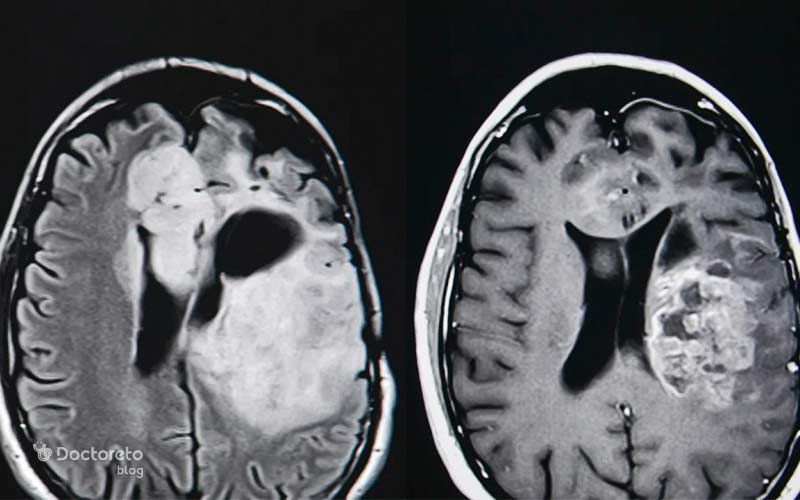

درصد بسیار نادری از بیماران بدون انتظار قبلی، کاهش چشمگیر یا حتی توقف کامل تومور را تجربه میکنند. این پدیده که در اصطلاح پزشکی «پسرفت خودبهخودی» نامیده میشود اغلب به دلیل فعال شدن ناگهانی سیستم ایمنی رخ میدهد. مطالعهای در Journal of Neuro-Oncology (۲۰۲۰) نشان داد که تعداد بسیار کمی از این بیماران پس از یک عفونت ویروسی یا تب بالا، کاهش قابل توجه تومور داشتند؛ زیرا سلولهای ایمنی T بهطور مؤثر سلولهای سرطانی را هدف قرار میدهند.

در جهان، چندین مطالعه علمی به بررسی موارد نادر «پسرفت خودبهخودی» تومورهای مغزی پرداختهاند. این پدیده در حدود ۱ درصد بیماران مشاهده میشود و اغلب در بیمارانی رخ داده که سیستم ایمنی آنها پس از عفونت یا واکسیناسیون خاصی فعال شده است.